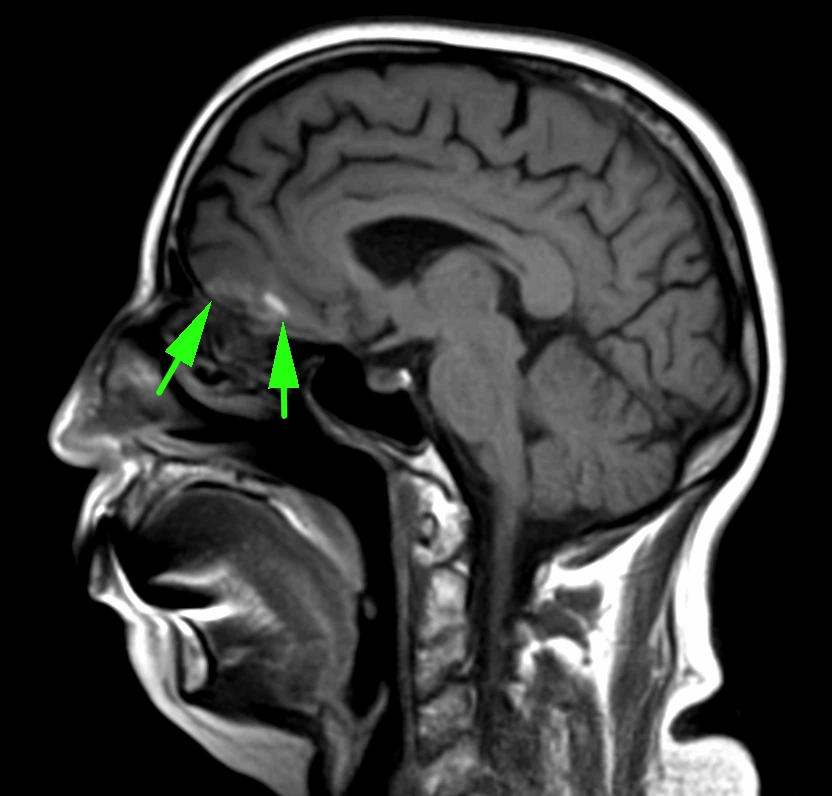

Снеговики бывают разные, но смысл симптома при аденоме гипофиза от этого не меняется: когда опухоль растёт вверх, она протискивается черезу дуральную селлярную диафрагму и в этом месте на ней явственно определяется поясок. Это, как утверждается, достаточно надёжный дифференциально диагностический признак (точность порядка 94-96%) именно аденомы гипофиза, а не какой-то другой опухоли данного расположения.